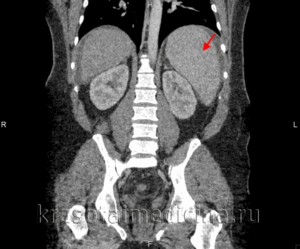

Спленомегалия. Увеличенная селезенка.

Спленомегалия — это увеличение размера больше 300 грамм и размера по длине больше 20 сантиметров. В свою очередь, увеличение органа больше чем 20 см и 1000 грамм, говорит об массивную спленомегалии

Один из наиболее информативных методов диагностики спленомегалии – УЗИ. Признаками спленомегалии на УЗИ является:

- увеличение размеров селезенки;

- при значительной спленомегалии – смещение соседних органов;

- при заболеваниях самой селезенки, спровоцировавших ее увеличение, наблюдаются ее неоднородная структура, изменения сосудов и так далее.

- компьютерная томография (Т);

- мультисрезовая компьютерная томография (МСКТ);

- магниторезонансная томография (МРТ).

В случае, если подтверждение спленомегалии необходимо, поскольку получены неоднозначные результаты исследования, методом выбора является ультразвуковое исследование в связи с его точностью и низкой стоимостью. КТ и МРТ позволяют более детально визуализировать селезенку. МРТ особенно эффективно при диагностике тромбоза портальной или селезеночной вены. Ядерное сканирование является точным методом и может идентифицировать дополнительную ткань селезенки, которую часто находят после спленэктомии из-за "рабочей гипертрофии" пропущенной ткани или фрагментов селезенки, высвобождающихся при ее разрыве во время операции. Иногда в брюшной полости могут быть обнаружены множественные остатки селезенки, часто эктопированные в соседнюю поджелудочную железу; такое состояние называется спленозом.